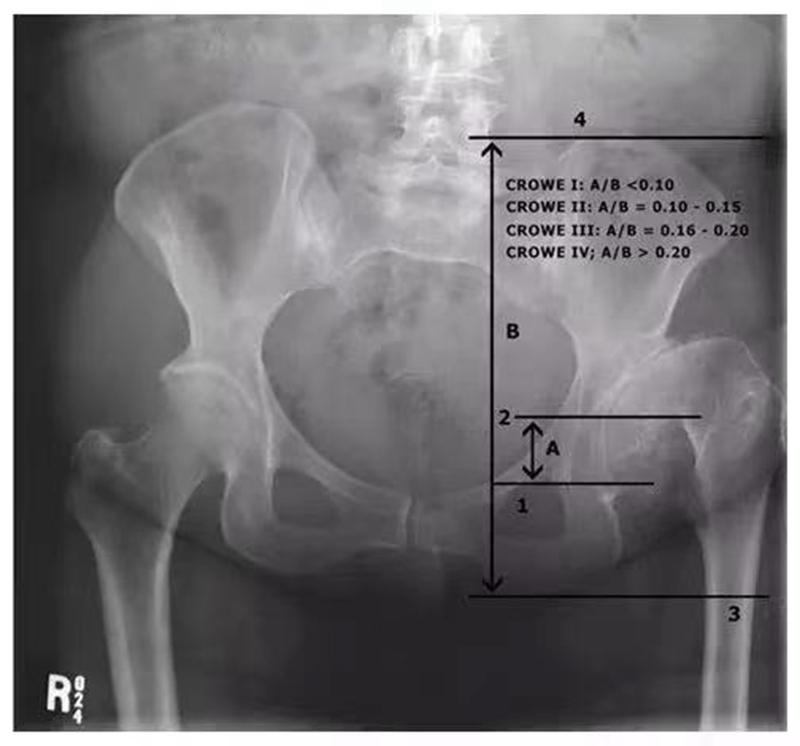

1、Crowe分型

Crowe于1979年提出的分型,能够较好地量化髋关节的半脱位程度,对临床手术决策具有重要的指导意义。其主要依据股骨头移位距离占股骨头高度百分比或者占骨盆高度的百分比进行划分。

Ⅰ型:不全脱位<50%;

Ⅱ型:不全脱位50%-75%;

Ⅲ型:不全脱位75%-100%;

Ⅳ型:不全脱位>100%,即完全脱位。